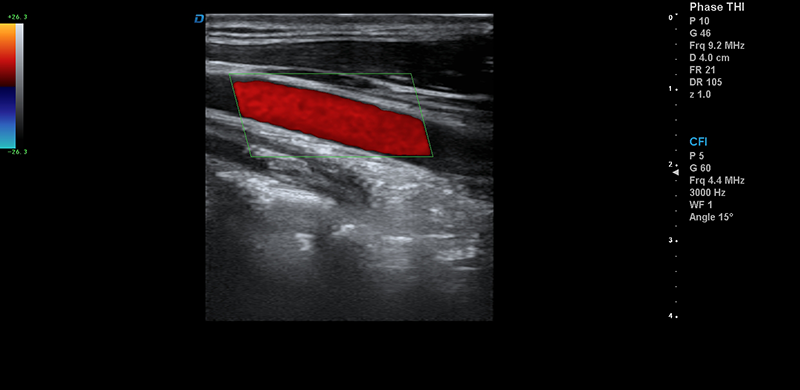

頸動脈血流